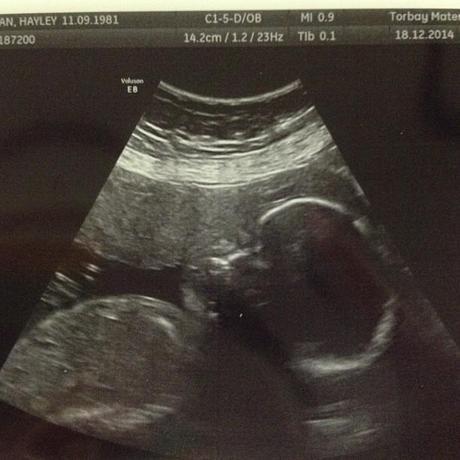

I had my 20 week scan, although for some reason it was done late at 23 weeks, and because of the babies position they weren't able to properly examine the heart or kidneys so I had to go back again a week later - on the second visit they were still having trouble but managed to examine the heart and one of the kidneys....they gave up on trying to find the other kidney but said they're sure its fine as everything seems to be functioning normally.